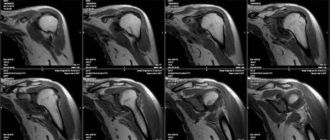

МРТ плечевого сустава

Мрт плечевого сустава — особенности процедуры, показания, расшифровка МРТ, или магнитно-резонансная томография – сравнительно